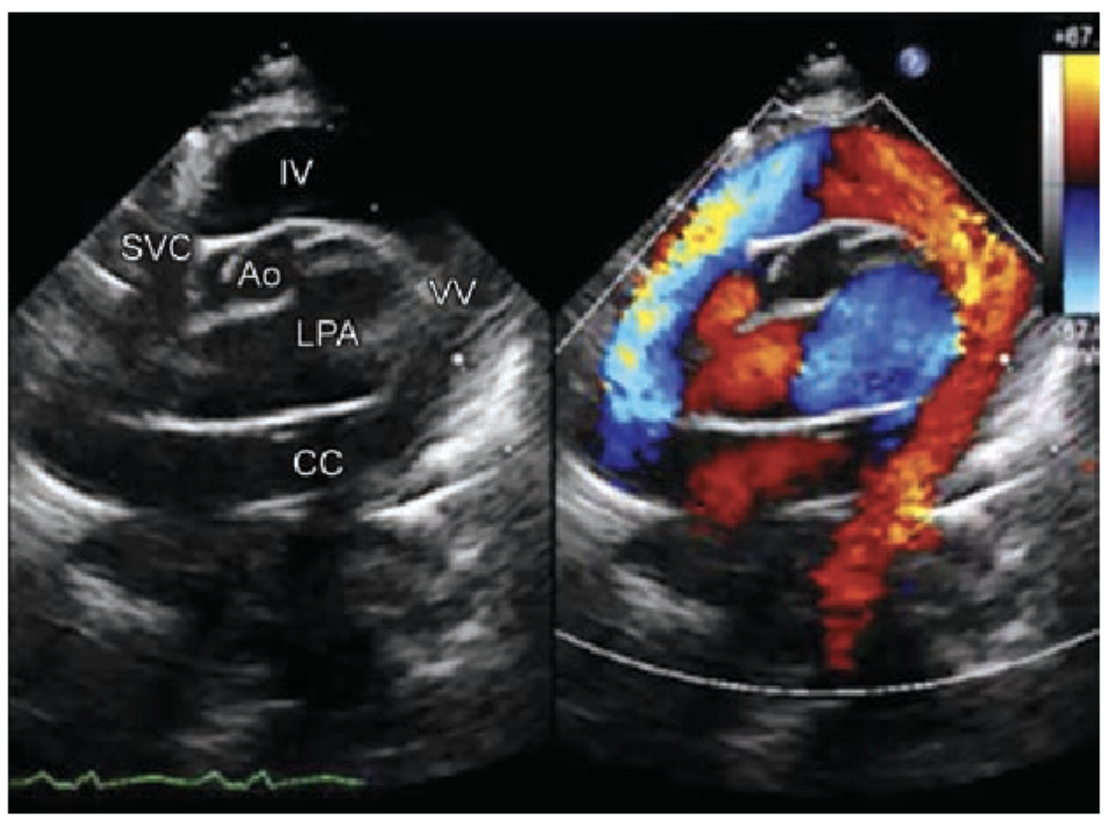

총폐정맥 환류 이상 (Total Anomalous Pulmonary Venous Return, TAPVR)

정의: 모든 폐정맥이 좌심방으로 연결되지 않고, 체정맥 순환이나 우심방으로 혼합된 후, ASD나 PFO를 통해 좌심방으로 유입되는 기형

분류: 연결 부위에 따라 4가지 형태로 분류

I형 (심상부형, Supracardiac): m/c, 수직 정맥을 통해 상대정맥으로 연결됨

II형 (심장형, Cardiac): 관상정맥동(Coronary sinus)으로 연결됨

III형 (심하부형, Infracardiac): 횡격막을 지나 간정맥이나 하대정맥으로 연결됨

IV형 (혼합형, Mixed): 두 가지 이상의 형태로 연결됨

CXR: 연장아의 심상부형은 snowman appearance를 보임

심초음파: 우심방/우심실의 확장, 비정상적 폐정맥 연결 확인하여 진단